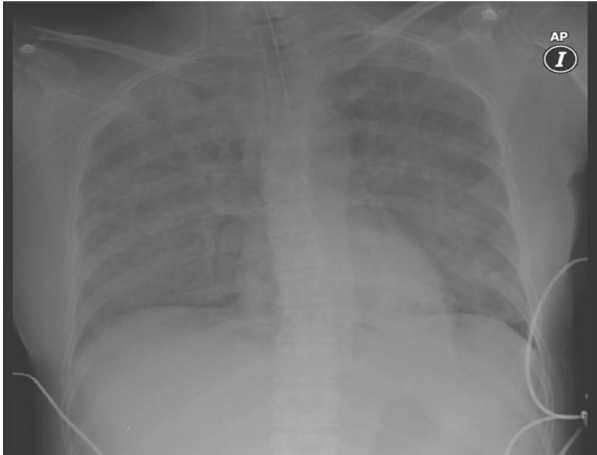

Approximately 500 cc of fluid was recovered through the ETT. Chest X-ray confirmed the diagnosis (Figure 1). Then she was moved to the ICU ward and sedation with Propofol 3 mg/kg/hr and Remifentanil 0, 5 mcg/kg/min were initiated. During treatment with PPV and PEEP, arterial pressured dropped to 80/50 and a dopamine infusion was initiated to keep MAP over 80 mmHg. 4 hours later, a second ABG showed improvement in the oxygenation and pH levels. Plasma electrolytes were: Na 144 mM, K 3, 0 mM, Cl 110 mM Ca++ 5.6 mg/dl. After a negative balance of 7 liters (Figures 2 and 3), respiratory parameters improved and she was extubated in the ICU 7 hours after the event. During the stay in the ICU she also presented dilutional anemia and coagulopathy that did not require transfusions (Hb 7, 4, Hct 26%, INR1.6; PT 44.7%, a PTT, 35 s.) She was discharged from the hospital 7 days later without any serious or irreversible neurological damage of any type.

Figure 2 Chest X-ray after respiratory parameters improved.

Figure 3 Chest X-ray after a negative balance of 7 liters.